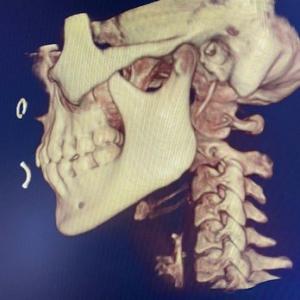

Dr. Rusty Lavender reviewing CBCT 3D image with patient

Neckwise implements CBCT imaging across all clinics, providing consistent three-dimensional upper cervical evaluation for structural assessment.

The integration of CBCT across all clinics reflects Neckwise’s commitment to maintaining consistent, objective, and measurable structural evaluation procedures. CBCT technology delivers detailed three-dimensional imaging, which is widely utilized in medical, dental, and chiropractic environments to visualize anatomical structures with clarity and minimal distortion.

CBCT imaging provides clinicians with a comprehensive three-dimensional view of the atlas (C1) and axis (C2) vertebrae, allowing for precise measurement of upper cervical alignment. Unlike conventional two-dimensional imaging, CBCT captures the spatial relationships of the upper cervical spine from multiple angles without overlap or distortion.

“When we can see the upper cervical spine in three dimensions, our analysis becomes more exact,” said Dr. Andrew Hall, co-founder of Neckwise. “CBCT allows us to determine how the atlas is positioned and how to approach correction with a higher degree of specificity.”